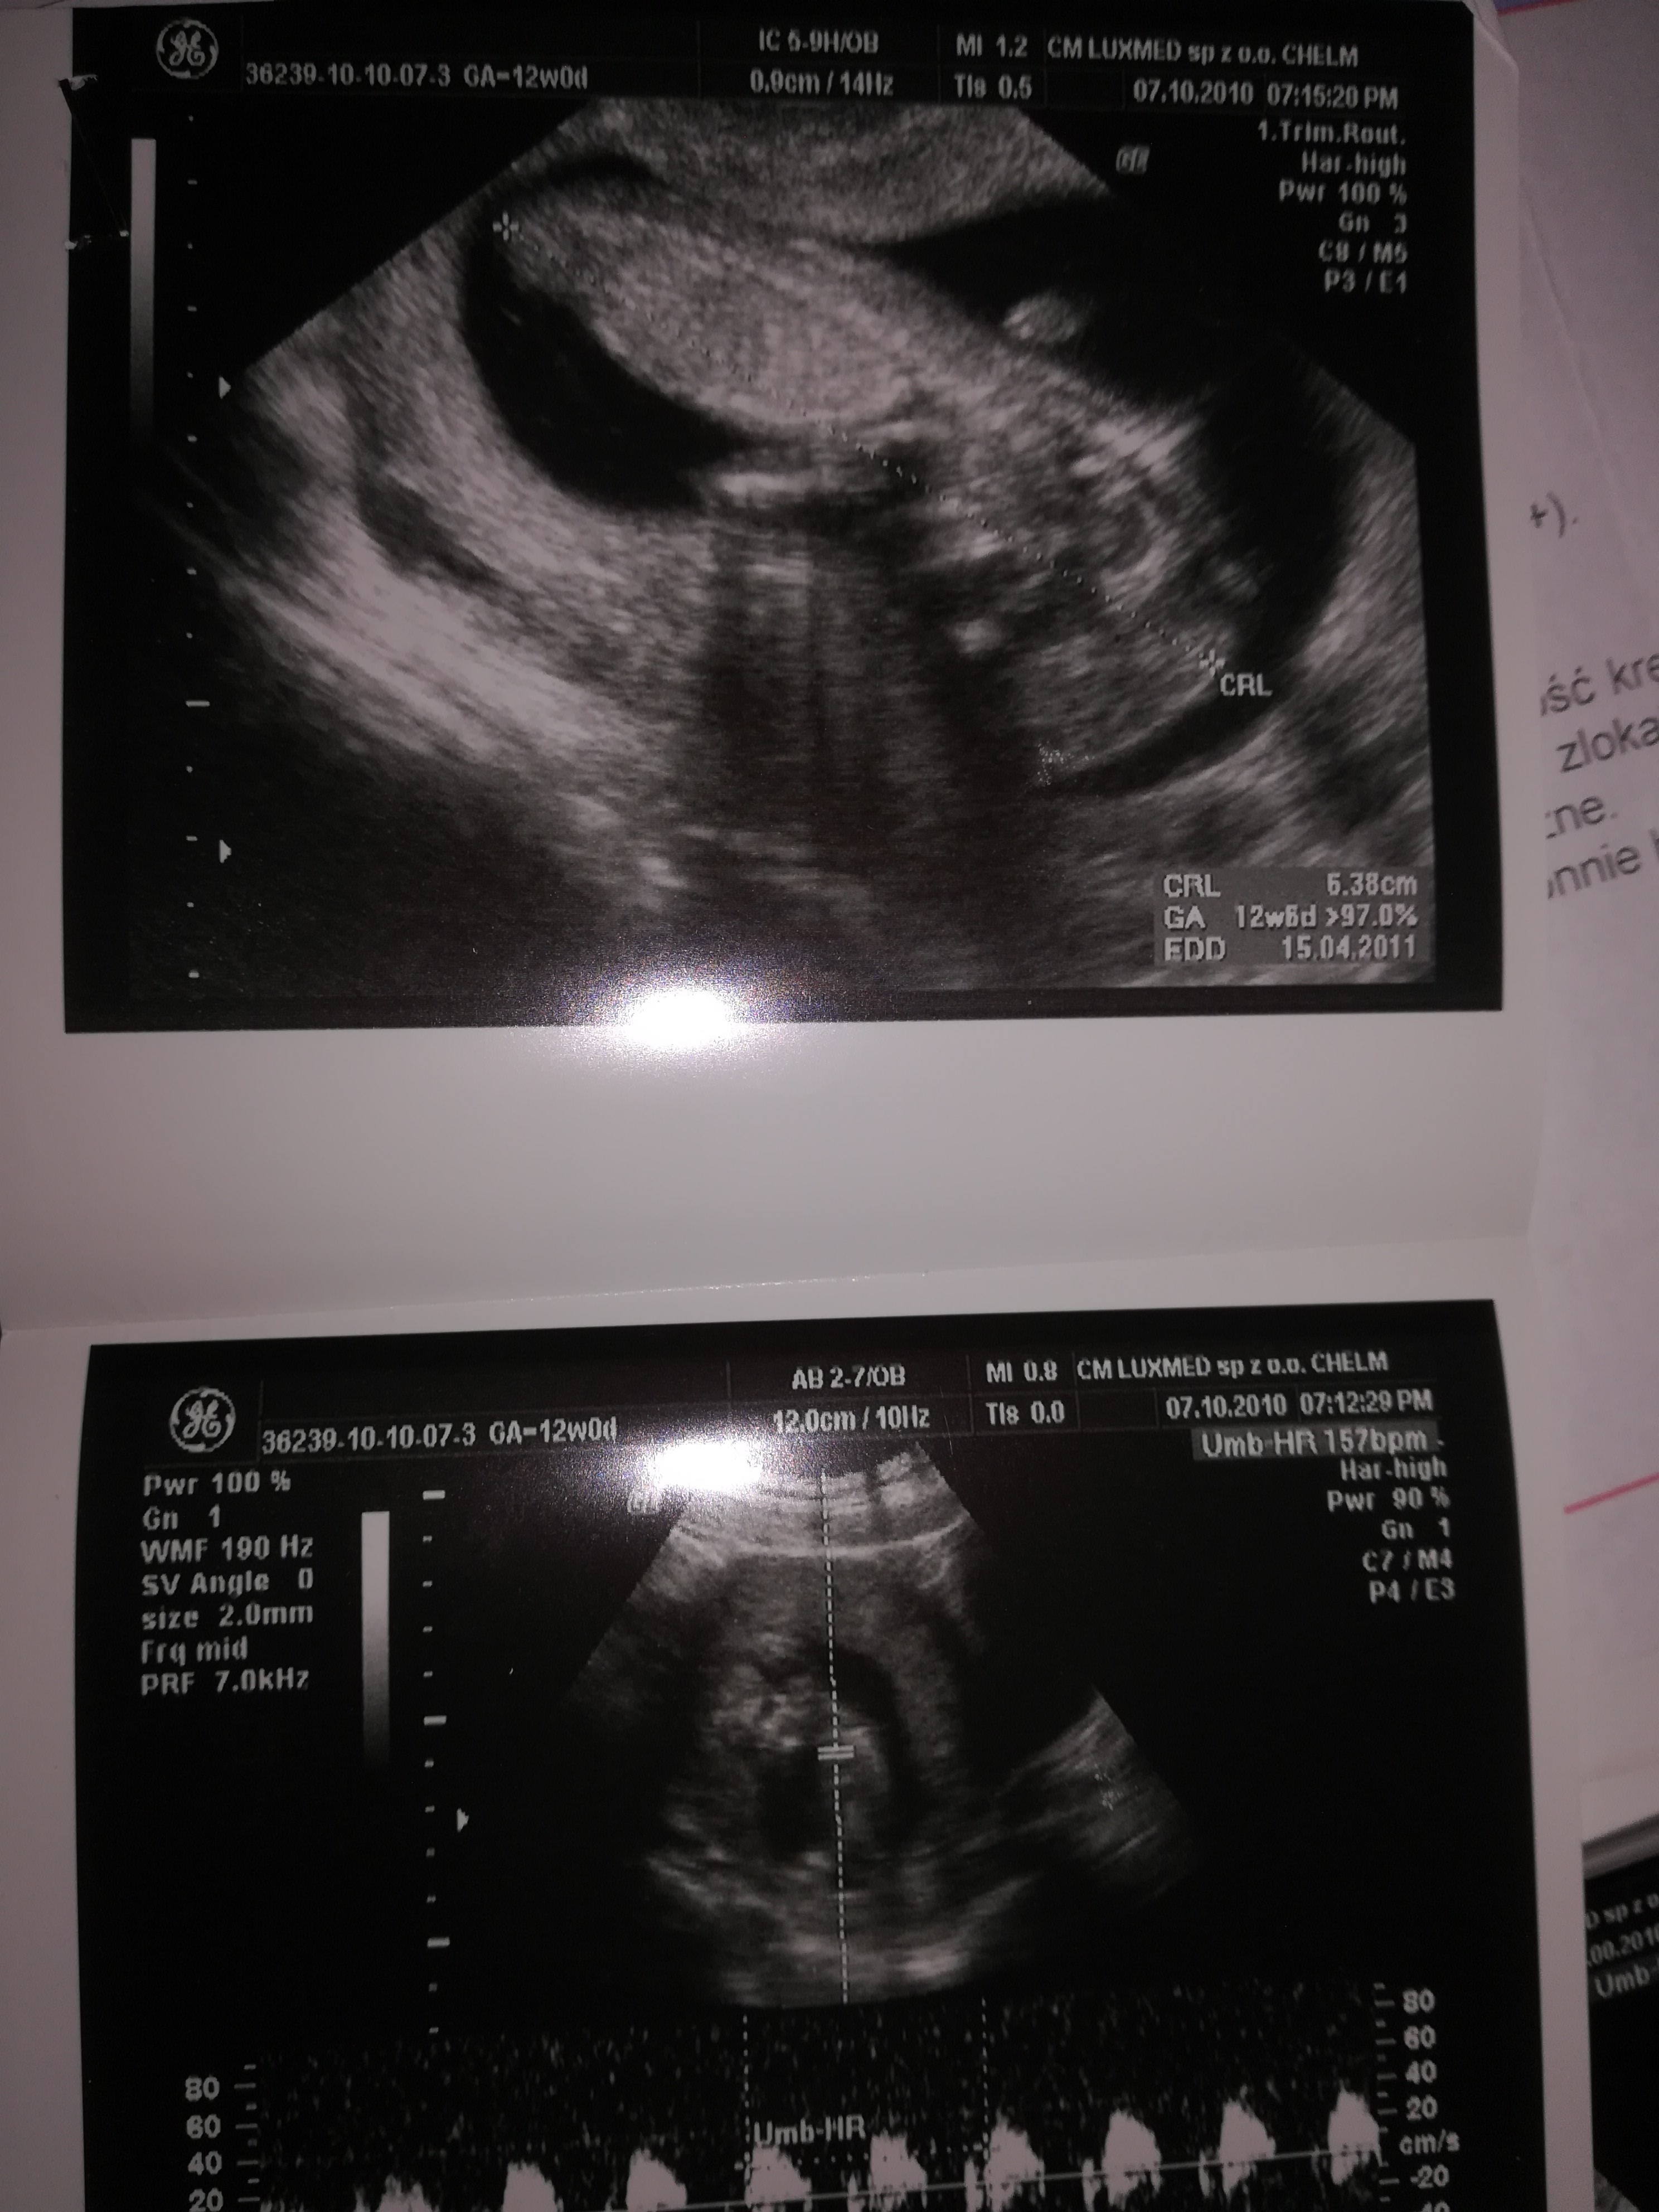

I w tym 5 tydzień 5 dzień mam zaznaczone że biło serduszko dlatego byłam zdziwiona jak poszłam na usg że nie było widać zarodka tylko pecherzyk.

Zobaczcie to usg córki z 5 tygodnia i 12 tygodnia i w tym 5 mam serduszko zaznaczone